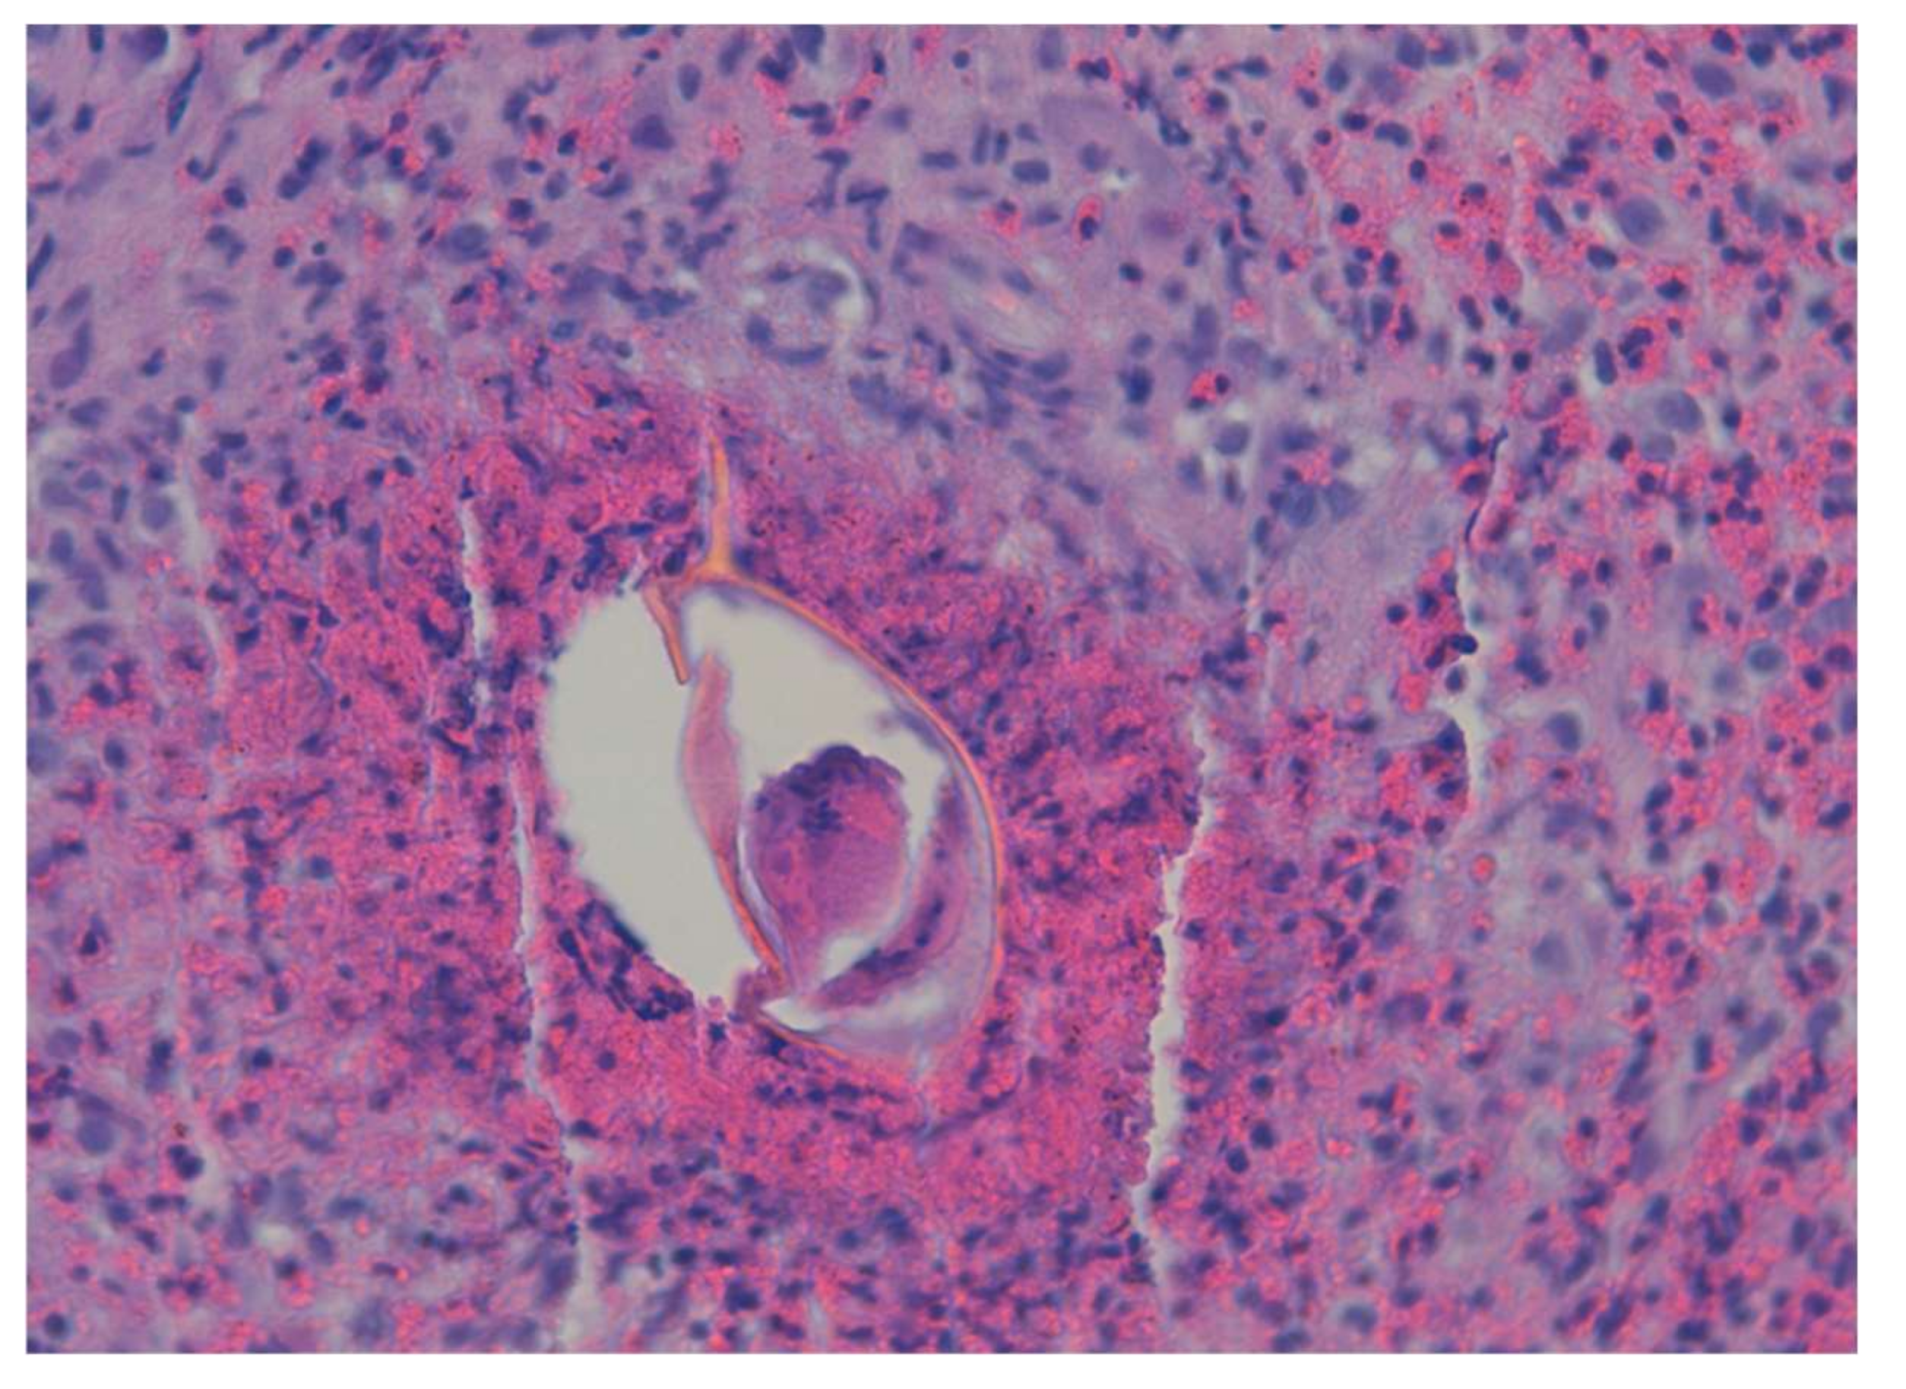

7. Neuroschistosomiasis

- Ferrari, T.C.A.; Moreira, P.R.R. Neuroschistosomiasis: Clinical symptoms and pathogenesis. Lancet Neurol. 2011, 10, 853–864. [Google Scholar] [CrossRef]

- Alves, W. The distribution of Schistosoma eggs in human tissues. Bull. World Health Organ. 1958, 18, 1092–1097. [Google Scholar] [PubMed]

- Ross, A.G.; McManus, D.P.; Farrar, J.; Hunstman, R.J.; Gray, D.J.; Li, Y.-S. Neuroschistosomiasis. J. Neurol. 2012, 259, 22–32. [Google Scholar] [CrossRef] [PubMed]